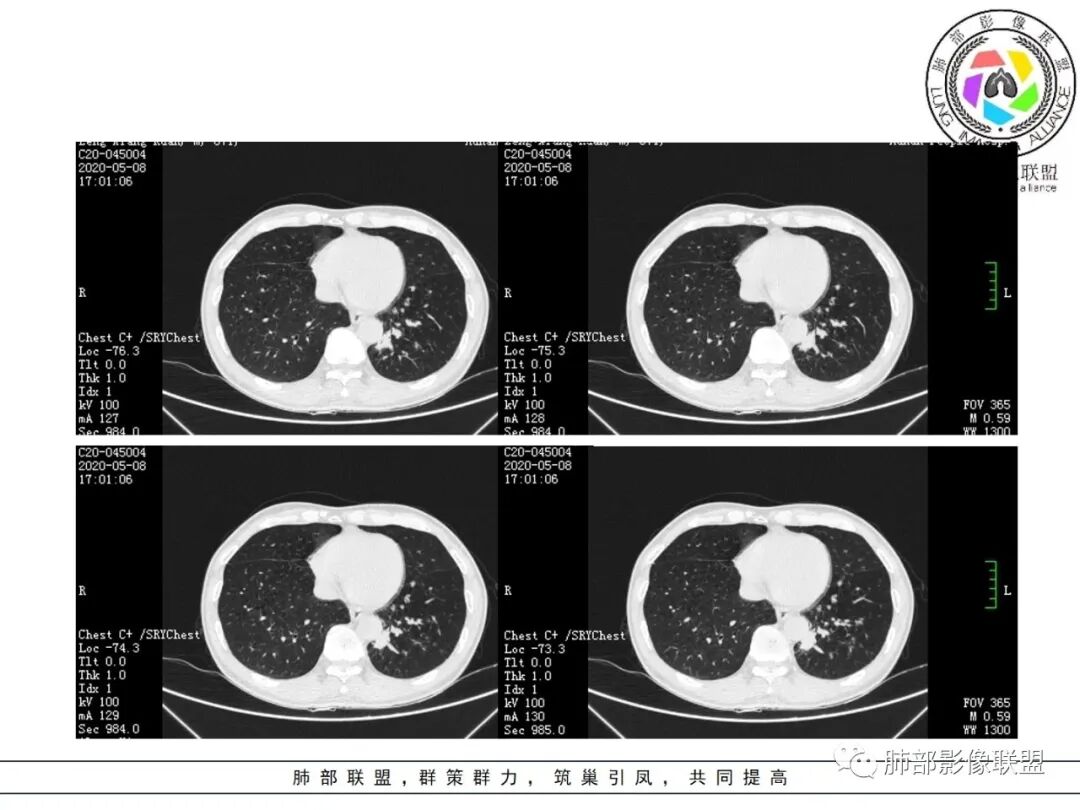

大雄:抗感染不吸收还是要警惕癌尤其主动脉旁的病灶红星:老年患者,咳嗽咳痰两个月,既往有糖尿病病史10年,左肺下叶后基底段斑片状、条索状、斑点状多形态的病灶,病灶内可见支气管征以及狭窄扩张的支气管影像。重建图像上可见到病灶沿支气管爬行。增强扫描病灶轻度强化,临近胸膜增厚。首先考虑感染性的病变,结核性的可能性最大。鉴别诊断上注意排除肺克以及淋巴瘤。三个石头:左肺下叶多发斑片,结节,条索,多态性?结核?多个结节边缘长毛刺,胸膜牵拉,分叶。矢状位支气管走行扭曲,没有完全阻塞,应该有粘液栓,有点像指状。主动脉旁病灶边缘平直,部分有鹏隆感,延迟强化。抗炎病灶变化不明显,结核?真菌?肿瘤也除外不了。没意见:左肺下叶基底段结节,膨隆、深分叶,毛刺,内侧串珠结节,中轴间质增厚,管腔狭窄,后基底段亚支不张,强化情况不明,考虑恶性,腺癌可能性大,另指套样征像,支气管壁增厚,不除外霉菌感染流心明智:老年患者,咳嗽咳痰2月。既往糖尿病史10年。胸CT:左肺下叶基底段多发结节影、斑片影、条索影,多数结节影沿支气管血管束分布,支气管壁厚,部分结节分叶、指状突,后基底段支气管狭窄闭塞。重建可见到病灶沿支气管爬行。增强扫描病灶明显强化,部分斑片影内可见低密度灶。普通抗感染无效。考虑:恶性病变,鳞?小?鉴别TB、隐球等。王秀仙:左肺下叶沿支气管血管束分布斑片、结节影,部分呈管状铸型生长,管腔狭窄,后基底段支气管阻塞,降主动脉旁不张实变,增强扫描病灶轻度强化,抗感染2周无吸收,考虑鳞癌。鉴别结核。蓝天白云:肺野内老年男性,咳嗽咳痰,有糖尿病病史,抗炎治疗无吸收。影像表现为左肺下叶支气管腔内结节影,支气管壁增厚,远侧小花小草,增强后实变影均匀强化,考虑鳞癌伴远端阻塞性炎症,鉴别结核。采莲:老年男性,咳嗽咳痰2月,有糖尿病史,左肺下叶沿支气管分布多发结节条状影,结节影不规则有分叶,成串珠样,靠下结节影成条索影,周围有空气储留,靠近主动脉不规则块状影,边缘平直,周围支气管壁增厚,支气管进入后阻塞,有糖尿病史,首选考虑炎性肺结核可能性大,鉴别肺鳞癌。了:左肺多发结节影,实性结节,,磨玻璃结节,左肺门结节影,深分叶,彭隆感,有血管滋养,考虑肿瘤,抗感染后病灶无吸收,感染不像,结节有强化,无卫星灶,结核可以排除不再涩的柠檬:老年男性,吸烟史,糖尿病史,咳嗽咳痰2月,抗感染2周无效。左下基底干及各分支管壁较弥漫增厚,伴支气管粘液栓,远端阻塞性肺炎,后基底段部分不张实变。先考虑感染病变,常规抗炎无效,需考虑结核、曲霉等,不能排除鳞癌合并感染,建议支气管镜检查。

尘缘:支气管壁增厚,沿支气管分布斑片状影,中远端支气管似堵塞,远端阻塞性改变,需要鉴别结核与肺癌,临床简单,镜检就行了。读片个人倾向于鳞癌伴感染吧。田园晚风:老年男性,有糖尿病史,咳嗽咳痰2月,左肺下叶沿支气管分布多发结节条状影,部分有分叶,成串珠样,靠下结节影成条索影,周围有空气储留,靠近主动脉不规则块状影,边缘平直,周围支气管壁增厚,支气管进入后阻塞,首选考虑肺癌可能性大,鉴别肺结核。

临床资料:老年男性,咳嗽咳痰2月余,慢性病史。有吸烟史40年(现已戒烟),抗感染治疗2周肺部病灶未见吸收。

影像所见:

肺气肿背景。

结节伴分叶。

斑片影,考虑阻塞性炎症。

支气管壁厚,支气管腔内高密度影填充。

周围散在斑片影及结节影,类似“小花花草草”的感觉。